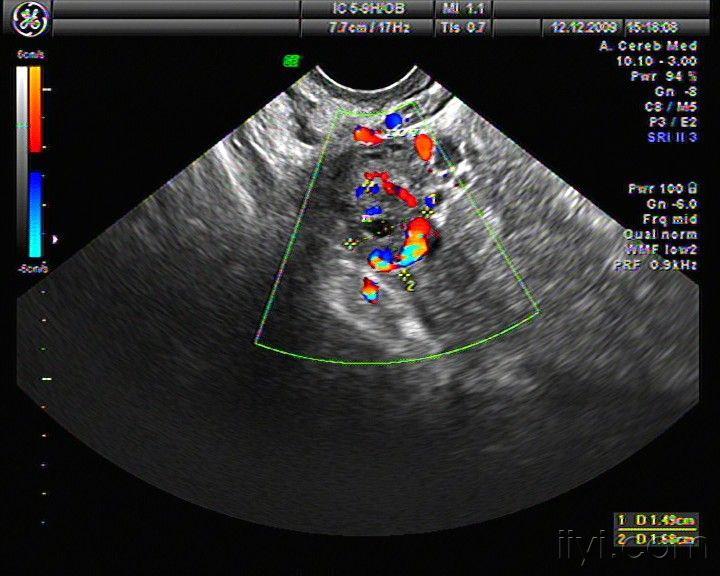

右侧卵巢内黄体血肿

图片尺寸720x576